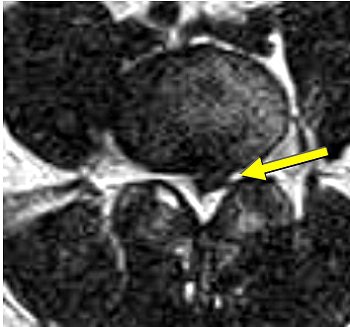

| Same patient as above. Top, transaxial T2-weighted image showed left L4 spinal nerve root compromise with axial loading (below). |